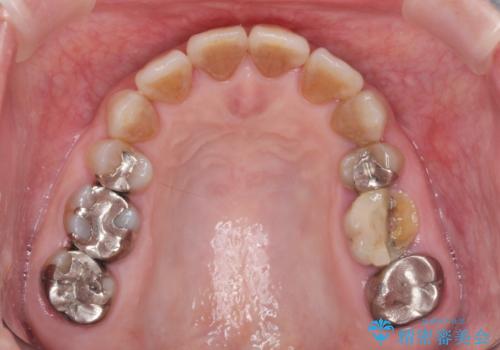

- ぐらぐらする歯や銀歯、なんとなくにおいのする奥歯の治療を求めて来院されました。

X線、歯周組織検査の結果、全体的に奥歯には重度〜中等度の歯周病の問題が見られました。

残すことのできない歯、予後の悪い歯を抜去し、ブリッジイ・ンプラントによる機能回復をおこなっていくと同時に、残すことのできる歯には歯周病治療をしっかりと行い、

将来に渡りしっかりと自分の歯で噛めるような口腔内環境を構築していきます。